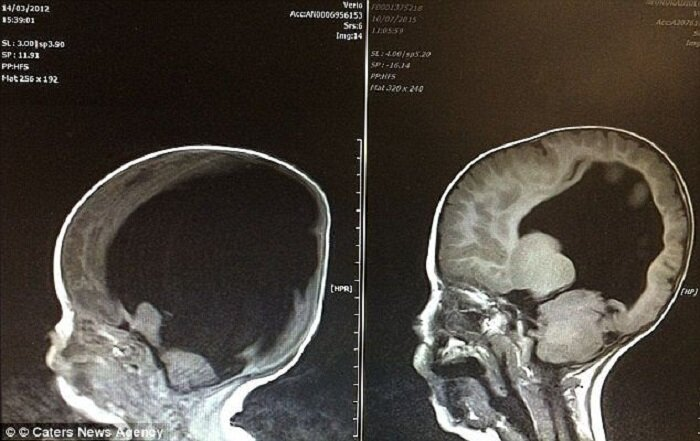

Самым удивительным было то, что ему удалось «отрастить» серое вещество. К трем годам объем мозга Ноя достиг 80%. Вскоре мальчик, которому еще до рождения, казалось бы, была уготована жизнь «овоща» неожиданно для всех заговорил. Но как так вышло?

Практически сразу после медицинского вмешательства произошло то, что многие до сих пор называют чудом. Оказалось, мозг Ноя не был полностью «отсутствующим» в буквальном смысле, как предполагали многие доктора. Ткани были сильно сдавлены жидкостью, которую «откачали». Как только это давление ушло, то мозг начал как бы расправляться и расти.